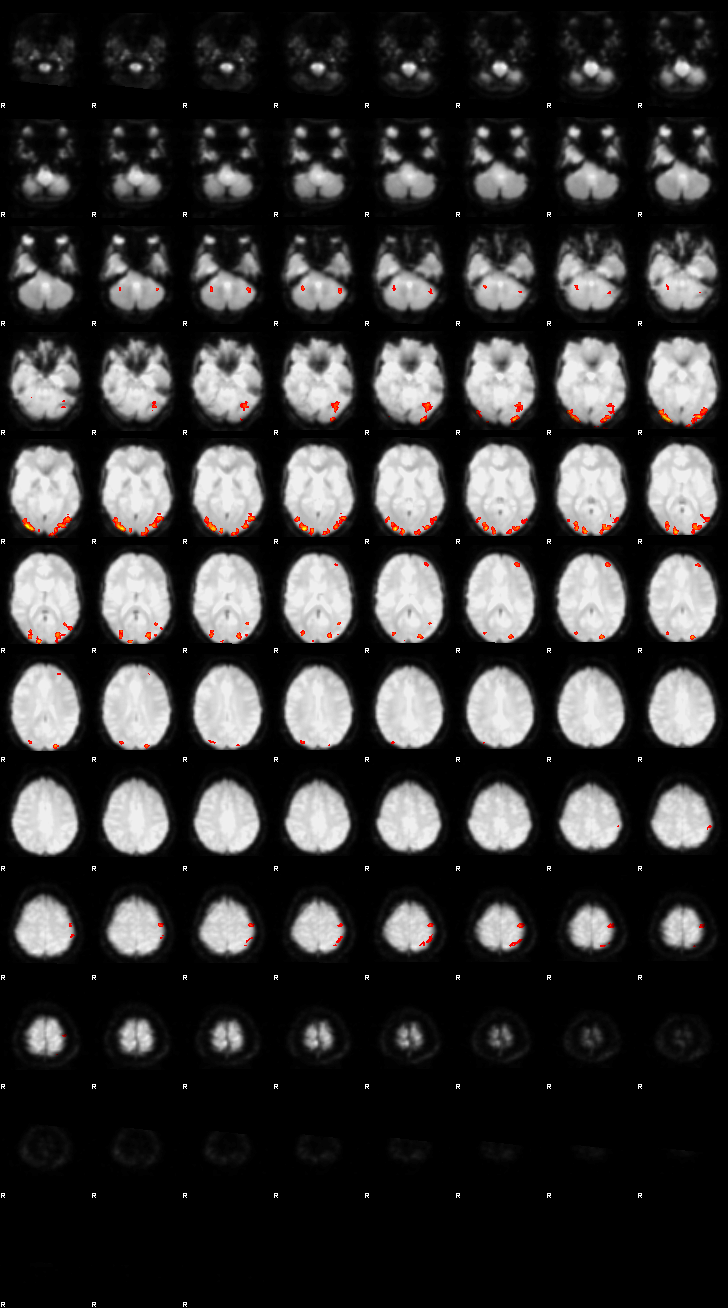

Visualization of First-level Design and Results (Run 1)#

Below, the design matrix and selected results from the first run are shown. Since both runs use the same design and contrasts, the results of the second run can be explored using the same approach.

Let’s now display the thresholded activation maps. A voxelwise threshold of Z > 3.1 was applied, followed by cluster-level correction at p < 0.05 (corrected for multiple comparisons).

zstat2 - C2 (congruent)

display(Markdown("#### Congruent"), rendered_thresh_zstats2)

Congruent